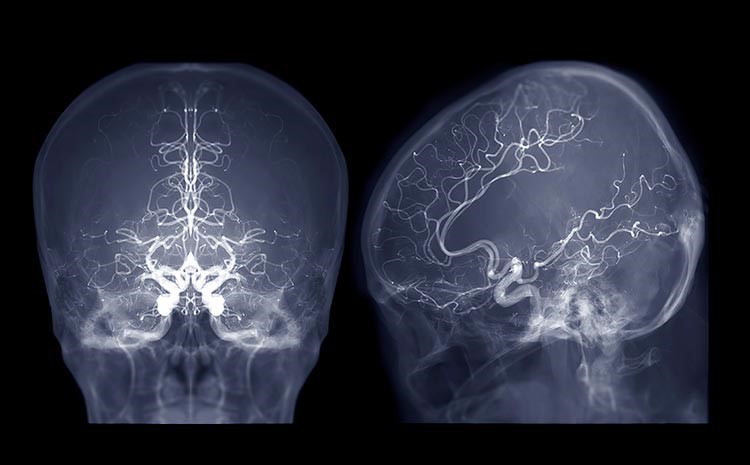

- AVC